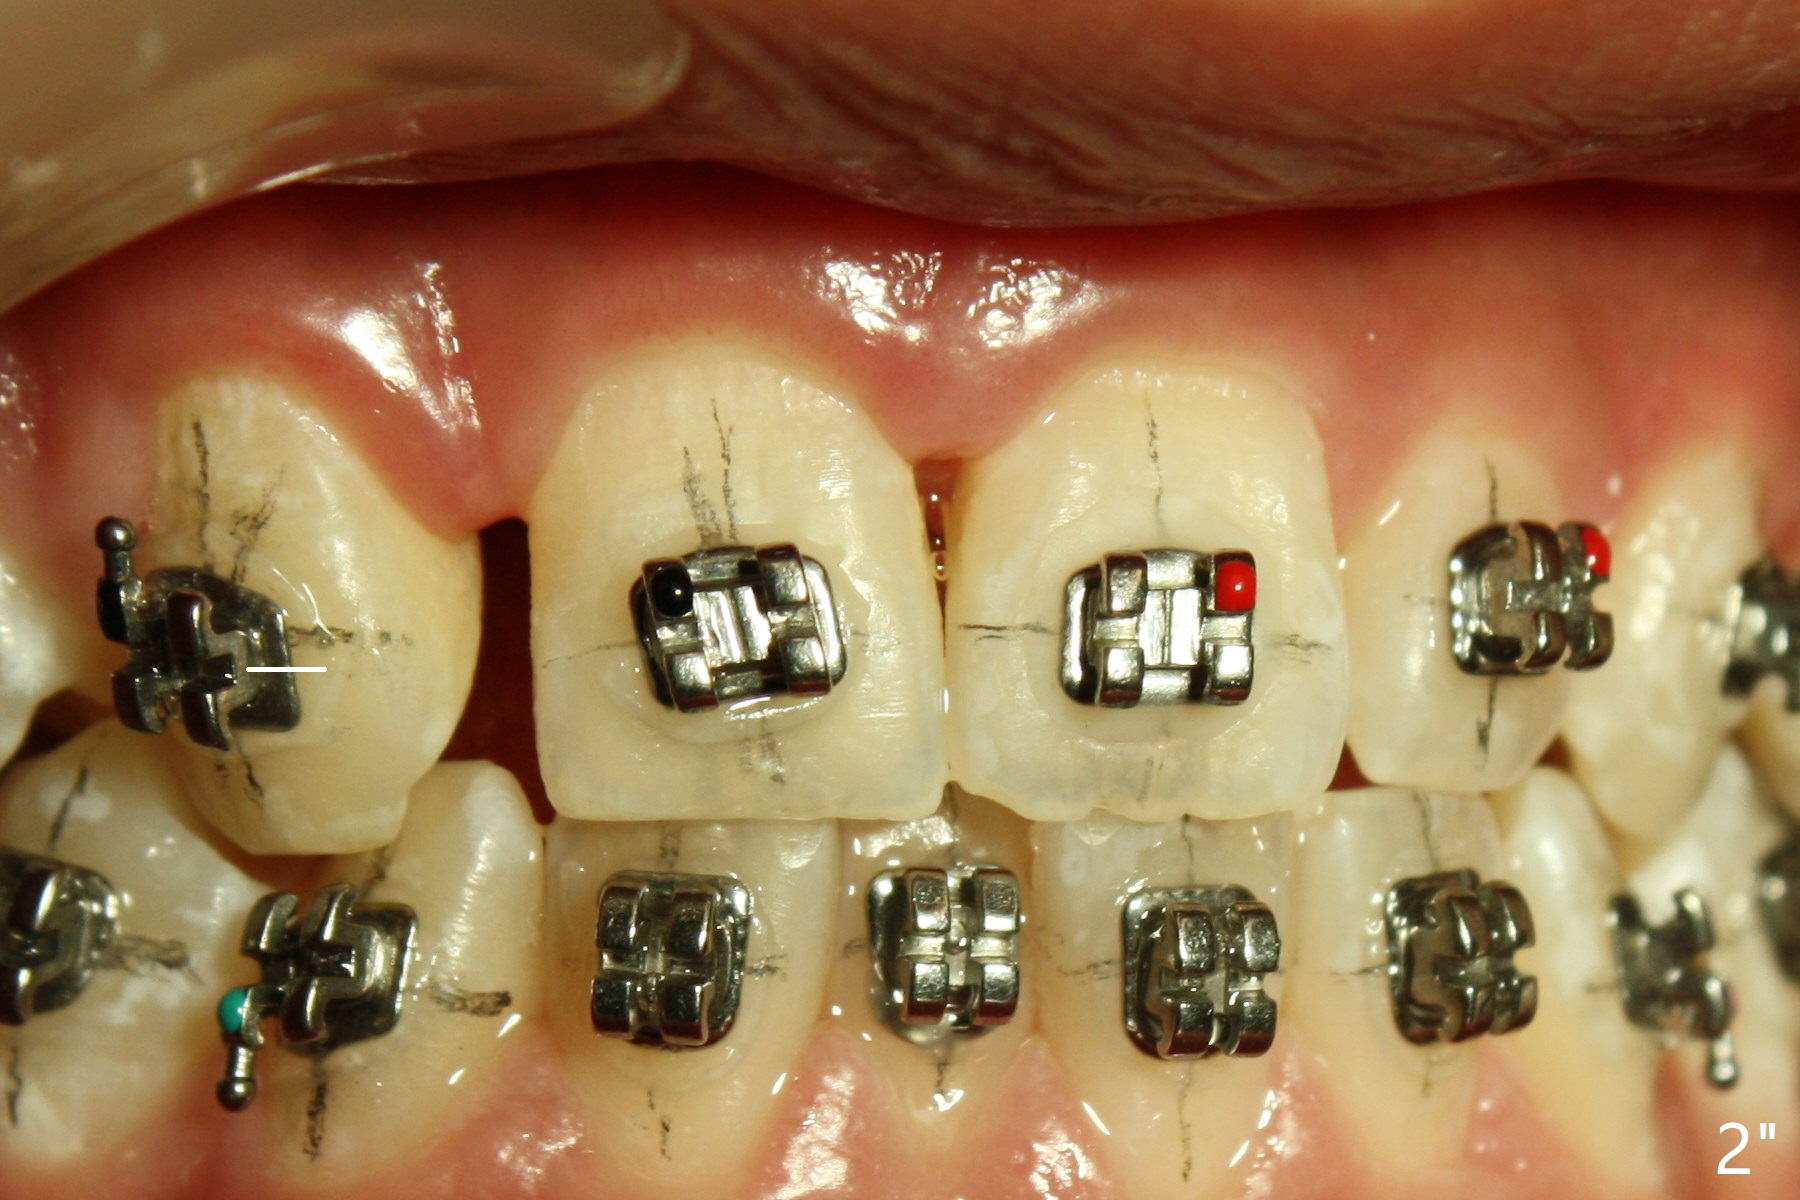

A 15-year-old man finishes orthodontic treatment for congenital missing lateral in 13 months. Molar Class I relationship remains the same (Fig.1,2,4,5). The upper diastemata mesial to 4s (Fig.4,7") close with correction of the upper midline deviation (Fig.2'-4'). The kid is unpleased with the elongated UR1 (Fig.2',3'). In fact it is a preexisting condition (Fig.2 arrow, 2"), but bracket placement at UR1 should have been overcorrected (incisal placement, Fig.3"). The intrusion should be done (Fig.4") before closure of the diastemata, since anchorage may be weakened when the separation between UR1 and 3 increases by using open coil spring. To prevent immediate relapse of the diastema between the upper central incisors, a fixed retainer is placed lingual before debracketing (Fig.6,6',6").